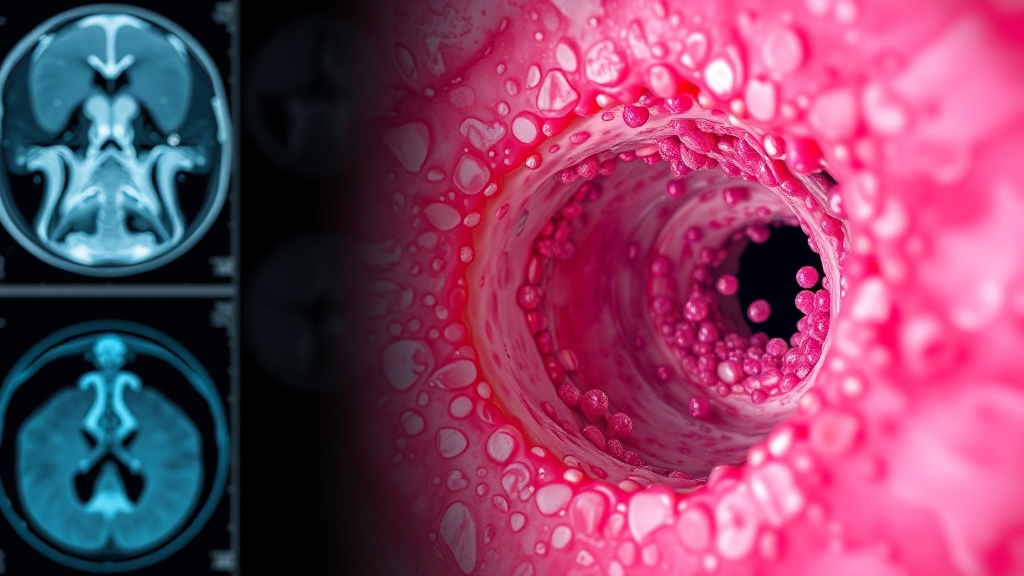

영상 검사 (CT, MRI)

CT, MRI로 종양의 위치, 크기, 주변 조직 침범 정도를 파악해요. CT는 뼈 구조를, MRI는 연부 조직을 선명하게 보여줘요.

코 내시경 검사

이비인후과에서 코 내시경 검사를 통해 코 안쪽과 부비동 상태를 직접 확인해요. 종양이 의심되면 조직 검사를 통해 암세포 유무를 정확히 판단하죠.